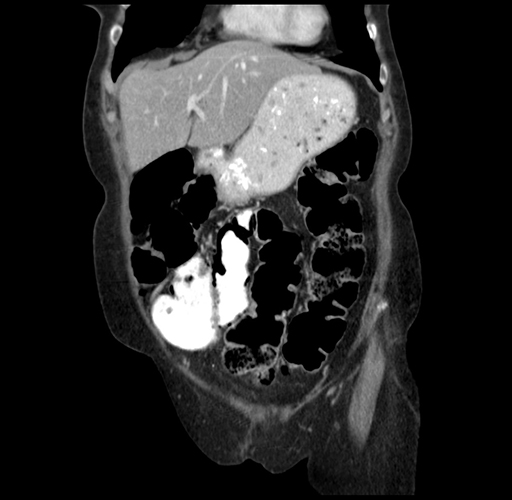

Pre-Chemo: Coronal Venous

Coronal Venous